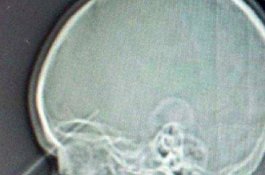

Ngilu... Mata Bocah Ini Tertusuk Pensil, Hampir Tembus Dahi dan Masuk Otak

News

- 27 September 2019 13:49